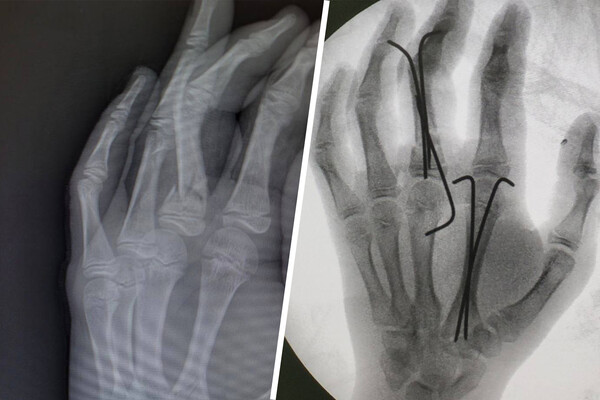

Юноша попал Московский областной центр охраны материнства и детства (МОЦОМД) с тяжелой травмой левой кисти после неудачного прыжка с тарзанки. У мальчика диагностировали открытый оскольчатый перелом среднего и указательного пальцев, а также большую рваную рану.

Врачи оперативно провели хирургическую обработку, восстановили костные фрагменты и зафиксировали их с помощью металлоконструкций, что помогло избежать серьезных осложнений.